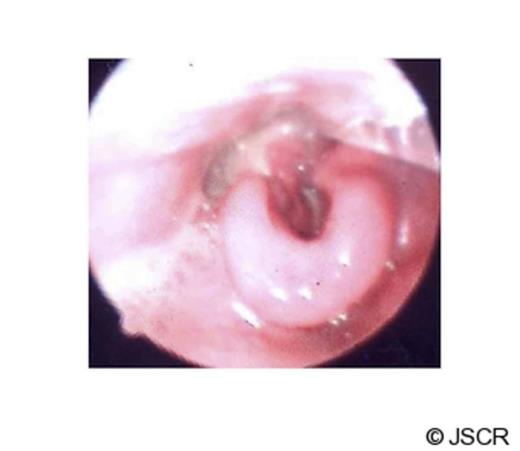

After the operation, the diagnosis was revised to isolated necrotizing fasciitis of the larynx. The necrosis of the larynx was closely monitored. A combination of empirical antibiotic therapy was prescribed under guidance of microbiologist (Table 1). The antibiotic regimen made significant improvements in the laryngeal oedema (Fig 2), resolution of necrosis and inflammation of the laryngopharynx.

On discharge (25th day of hospital stay), there was no dysphagia, dysphonia or dyspnoea. The necrosis of the larynx was fully resolved and the laryngeal skeleton was intact. Mucosal regeneration was complete and vocal cords were normal.